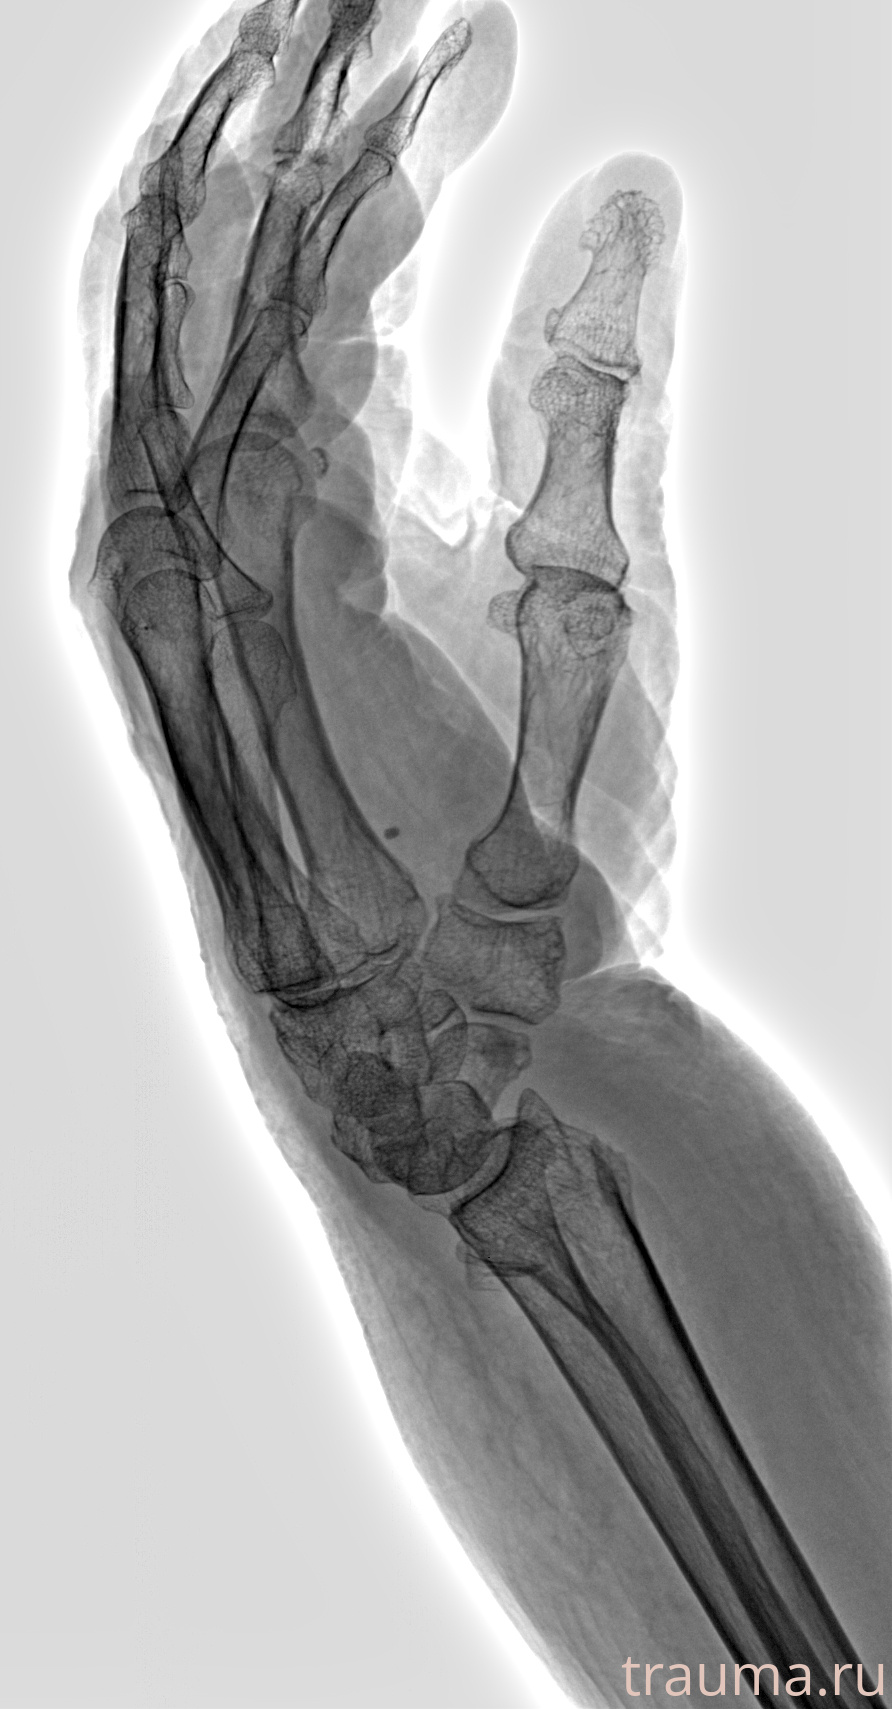

Рентген на дому: по вашему адресу приезжает врач-рентгенолог, травматолог-ортопед с мобильным рентгеновским аппаратом, проводит диагностику травмы или заболевания, делает необходимые рентгенограммы, дает рекомендации по дальнейшему лечению. Получить качественные снимки в домашних условиях возможно благодаря уникальной методике, разработанной МосРентген Центром для института  Склифосовского